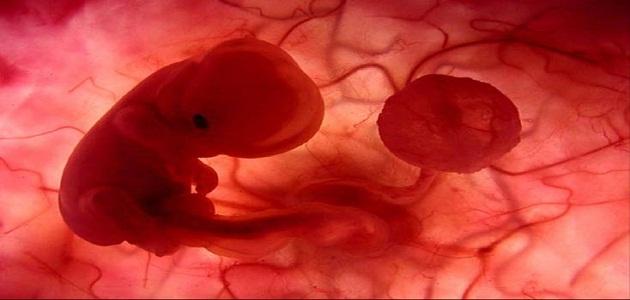

فالجنين في الشهر الأول، ما هو إلا نقاط متجمعة من الدماء، وإن قامت المرأة بشرب الكثير من السوائل الساخنة أو حتى الاستحمام بالماء الساخن فإنّ ذلك قد يعرضها لفقدان الجنين، لأنه في مرحلة صغيرةٍ جداً، ولا يمكن أن نحتسبه أنه إنسان، وعليه لا بدّ من التعامل مع هذه النقطة والتوقف عن الاستهتار.